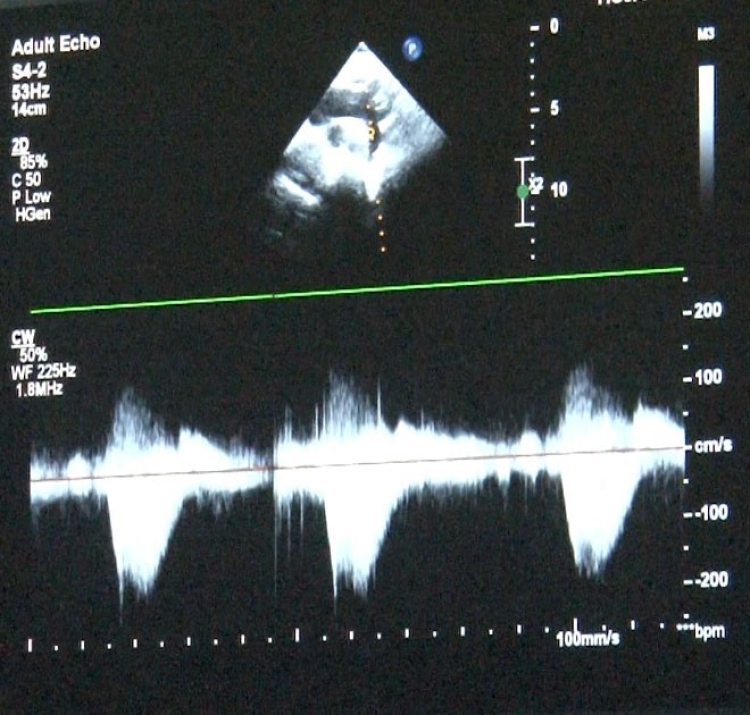

‘Sağlık Bakanlığı verilerine göre her yıl bin canlı doğumdan 8'inde doğumsal kalp hastalığı görebilmekteyiz' diyerek sözlerine başlayan Uzm. Dr. Damla Gökçeer Akbulut, "Yılda 12 bin çocuk doğumsal kalp hastalığıyla dünyaya geliyor. Çeşitli nedenleri olabiliyor bazen annenin gebelikte kullandığı ilaçlar ya da diyabet gibi bir hastalığı olması, genetik rahatsızlıklar, bunlar genetik olarak kalp rahatsızlıklarına yol açabiliyor. Bu hastalarda erken tanı mümkün, daha anne karnındayken fetal ekokardiyografi (anne karnındaki bebeğin kalp yapısını ve işlevini değerlendirmek amacıyla kullanılan bir tıbbi görüntüleme)yle doğumsal kalp hastalığı olan bebeklerde doğum sonrası erken müdahale yapabiliyoruz. Bazı bebekler mor doğabiliyor ancak bazılarında bu bulgular ilk ay içinde gelişebiliyor" dedi.